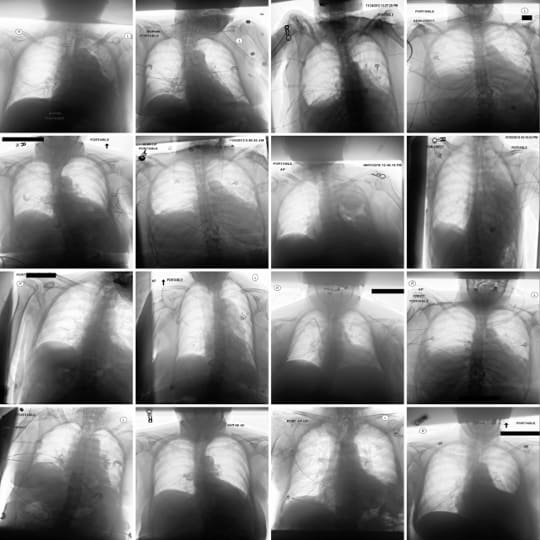

We train Sparse Autoencoders (SAEs) on the class token of a radiology image encoder, on a dataset of chest x-rays. We use the trained SAE, in conjunction with automated interpretability, to generate radiology reports. The final radiology report represents a concatenation of the text descriptions of activate SAE features. We train a diffusion model to allow causal interventions on SAE features. This diffusion model enables us to highlight where in the chest x-ray each sentence in the radiology report comes from by localising changes in the image post-intervention. Our method achieves competitive accuracy in comparison to state of the art medical foundation models while using a fraction of the parameter count and compute costs. To the best of our knowledge, this is the first time SAEs have been used for a non-trivial downstream task - namely to perform multi-modal reasoning on medical images.

Radiological services are essential to modern clinical practice, with demand rising rapidly. In the UK, the NHS performs over 43 million radiological procedures annually, costing over £2 billion, and demand for scans more than doubled between 2012 and 2019. A significant portion of these costs addresses rising demand through agency, bank, and overtime staff, but a national imaging strategy notes this funding is unsustainable. Consequently, there’s growing interest in (semi)-automating tasks like radiology report generation, augmentation, and summarization to assist clinicians, spurred by advances in multimodal text-vision modelling techniques.